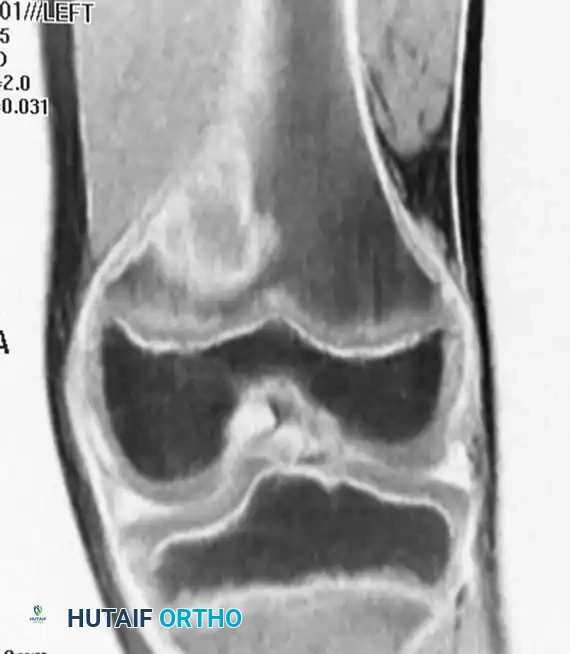

Fig. 20-9 A, B, and C: Eight-year-old boy with a cortical desmoid of the left femur. Anteroposterior radiograph (A) and corresponding Coronal (B) and Axial (C) MRI scans revealing cortical erosion with a sclerotic base.

The lesion is optimally visualized on an oblique radiograph with the lower extremity externally rotated 20 to 45 degrees. Advanced imaging (MRI) demonstrates focal cortical erosion with a thickened, sclerotic base and adjacent soft-tissue edema.

Clinical Pearl: The cortical desmoid is a classic "do not touch" lesion. Because its radiographic and MRI appearance can mimic early osteosarcoma or periosteal reactions, recognizing its exact posteromedial location is critical. Biopsy is strictly contraindicated, as the reactive histological features can be misinterpreted as a malignancy. No treatment is necessary.